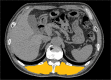

Patients and methods: A total of 99 patients without COPD and 201 patients with COPD, with a smoking history of more than 10 pack-years were enrolled in this study, and serum Cr and CysC levels were measured. On chest high-resolution CT images, %low attenuation area (LAA%) (≤960 Hounsfield units (HU)) and ESMCSA at the Th12 level were identified.